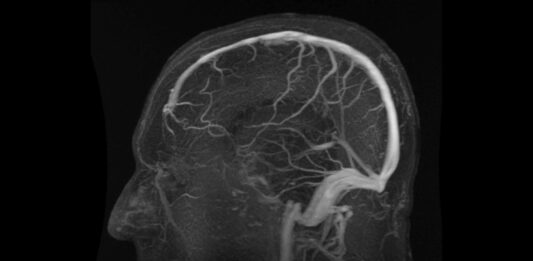

Un innovador estudio de USC revela que la clave para diagnosticar el Alzheimer podría estar en el flujo sanguíneo cerebral, no en las proteínas tóxicas.